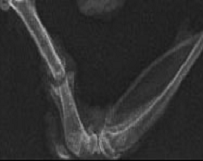

Рентгенологически на 30 сут. эксперимента в 5 случаях отмечается активное формирование костных структур, ранняя перестройка костной мозоли, восстановление целостности кортикальной пластинки и частичное восстановление костномозгового канала. Линия остеотомии отчетливо прослеживается в одном случае (рис.11).

Рис.11. Типичная рентгенограмма бедренной кости крысы группы 4 через 30 суток после остеотомии и общего равномерного гамма-облучения 3,0 Гр. Воздействие НАК - модулированная частота - несущая частота 5 Гц с частотой наложения 200 Гц.

Оптическая плотность зоны регенерата - 0,501 ± 0,012, р < 0,05.

На 30 сут. эксперимента в межотломковой щели определяется зрелая фиброретикулярная ткань с меньшим количеством тканевых кист, небольшим количеством тонкостенных сосудов с единичными лимфоцитами и макрофагами, меньшим количеством по сравнению с 3 группой зрелых и незрелых костных балок. Контуры краев отломков не отчетливы. В кортикальной пластинке прослеживается увеличение по сравнению с 3 группой числа расширенных сосудистых каналов. Периостально - небольшая фиброзно-хрящевая мозоль с включением более зрелых костных балок (рис.12).